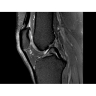

МРТ аппарат GE Optima MR450w 1.5T

МР-томограф с широким туннелем Optima MR450w является настоящей рабочей лошадкой и может эффективно обслуживать большее число пациентов. Томограф обеспечивает одновременно удобство пациента, продуктивность работы, отличное качество изображения. В этой МРТ-системе инженерам компании удалось без компромиссов совместить необходимый объем перемещения с удивительно высоким качеством изображения.